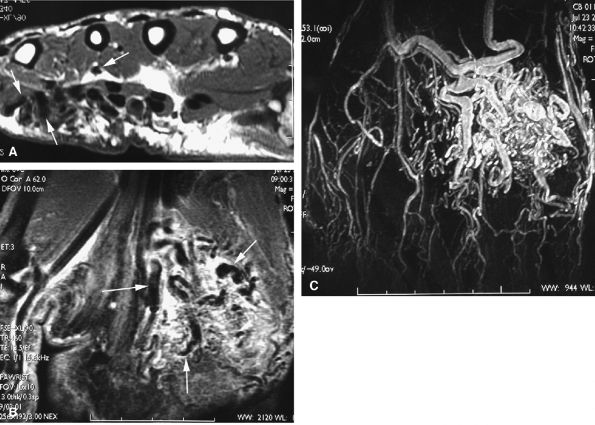

FIGURE 11.80 ● Arteriovenous malformation. (A) Axial T1-weighted image, (B) coronal post-contrast fat-suppressed T1-weighted image, and (C) MR angiogram showing a high-velocity vascular malformation of the hypothenar eminence with flow void artifacts (arrows). The angioarchitecture is better assessed with MR angiography.